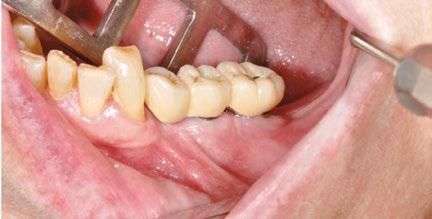

Our patient is consulting for pain in the right mandibular molar region and difficulty chewing (Figure 3).

Figures 2A and 2B: Panthera Dental platform interface; vestibular (2A) and lingual (2B) views of the subperiosteal implant Figure 3: Initial panoramic image Figures 4A-4C: Visualization of the subperiosteal implant in relation to the mock-up

not to undergo long and complex implant treatment. Her request is first and foremost functional. Esthetics and price are secondary concerns. We therefore offer the following treatment plan: keep the malpositioned anterior mandibular teeth with only mild gingivitis, rehabilitate the left posterior mandibular region with a subperiosteal implant, extract molars 47 and 48, and reassess the best implant solution for this region after healing.